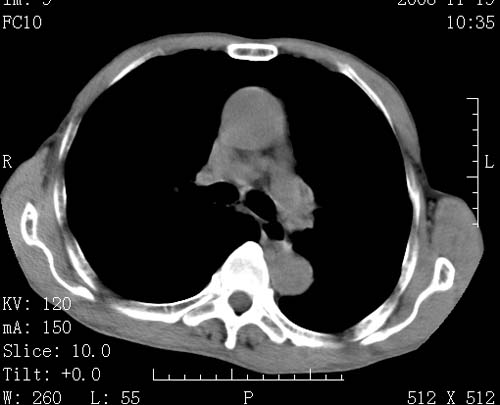

标题: CT16691:m 67 胃镜确诊食管下段及贲门癌 [打印本页]

标题: CT16691:m 67 胃镜确诊食管下段及贲门癌

术前查体,双肺部结节是转移?结核?请点评

1)符合食管癌表现。2)两肺及纵隔淋巴结多发性转移瘤。3)左肺上叶舌段及两肺下叶炎症感染。